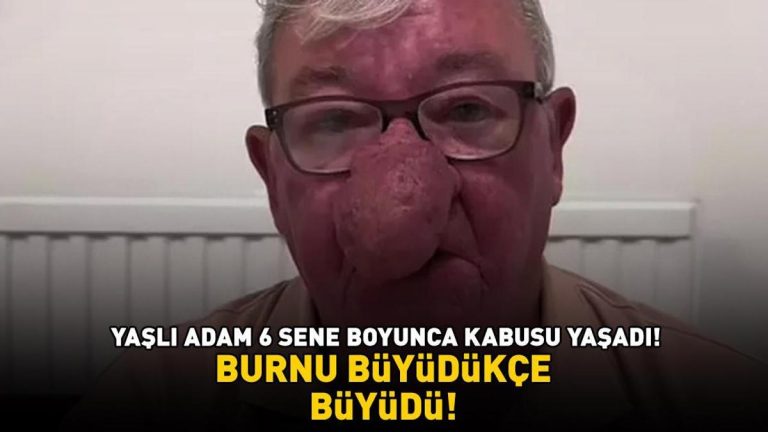

İhmal edilen ve tekrarlayan boğaz ağrısına dikkat! Birçok hastalığın habercisi olabilir…

Kalbinizi dinleyin: Bu şikayetleri hafife almayın! Kapalı bypass yöntemi nedir?